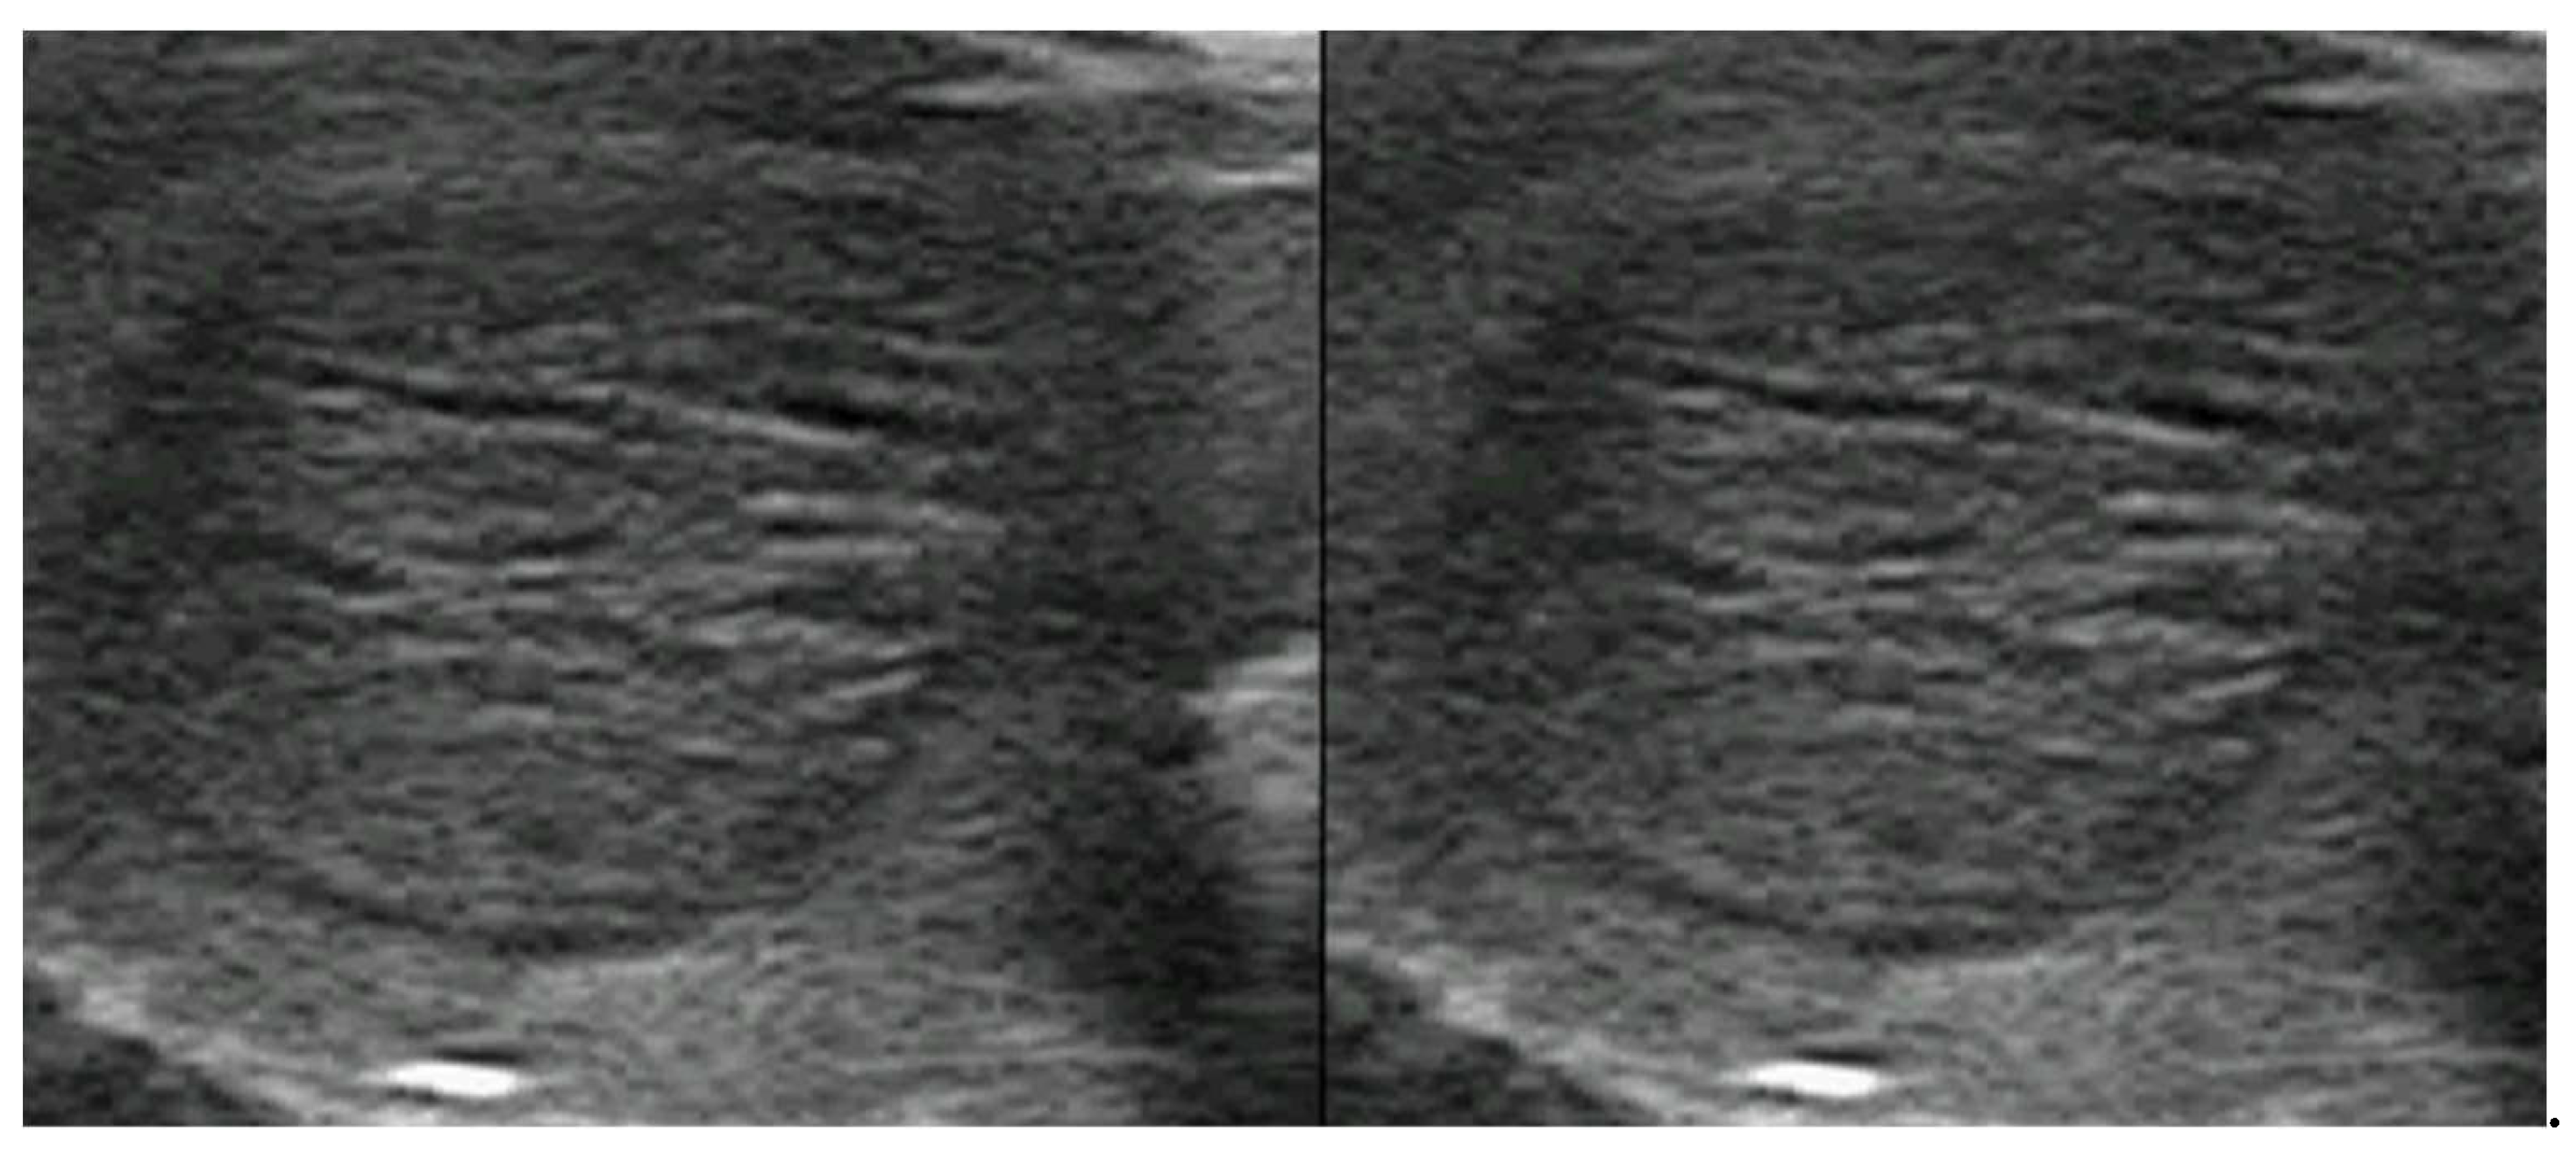

3.4. Hypothyroidism